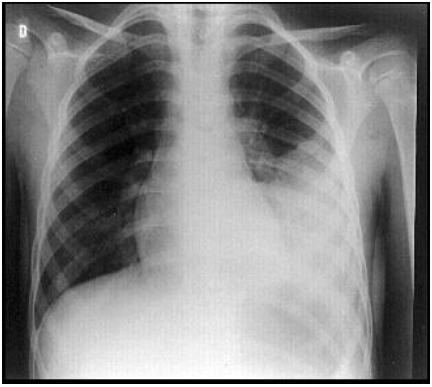

Homem, 24 anos, apresenta tosse, expectoração purulenta, dor torácica ventilatório-dependente à esquerda, febre (39,6ºC.) e calafrios. O radiograma de tórax é mostrado abaixo.

Em relação aos achados do radiograma do hemitórax esquerdo (no lobo inferior), é correto afirmar que se trata de